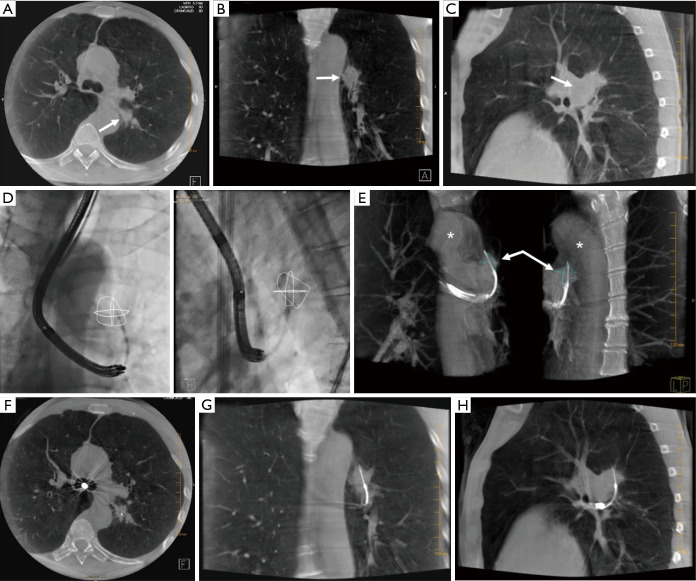

Figure 5.

CBCT and tumor segmentation. Top Row (A,B,C) shows baseline CBCT images acquired before bronchoscope insertion. In the middle row (D), CBCT augmented fluoroscopic overlay demonstrates a virtual image of the segmented tumor (D). An AP image (left) and Lateral image (right) are shown. (E) VRT images can enhance the view of bronchoscopic tools, lesions and surrounding structures. On the bottom row, CBCT demonstrate transbronchial needle located within target lesion in three orthogonal planes (F,G,H). Arrows indicate the target tumor, asterisks indicate the Aorta. CBCT, cone beam computed tomography; VRT, volume rendering technique.

When utilized for planning and navigation, CBCT is acquired early in the procedure, after anesthesia is administered but typically before the bronchoscope is inserted. Images are reviewed and the target PPLS are located, then outlined using dedicated segmentation software (Figure 5) (7,8,11,25). Most systems have either manual and/or semi-automatic segmentation tool that allow the user to outline a lesion on CBCT images (in one or more planes) or perform a volumetric segmentation of a lesion. The segmented lesion can then be overlaid on live fluoroscopic images to provide a target for intraprocedural navigation and sampling.

All available segmentation tools provide only a static overlay, although the underlying anatomy they represent will move with respiration. Thus, the overlay only matches the true lesion location at a single point in the respiratory cycle, coincident with the location during CBCT acquisition. This can be misleading, especially in cases where the lesion is not visible on fluoroscopy. PPLS motion has been reported to average 1.7 cm over all lung regions, although the range of PPLS motion is more pronounced near the base of the lung, where lesion motion over a breathing cycle averages 2.5 cm (33). Hohenforst-Schmidt and coworkers were the first group to report the use of airways segmentation overlaid on fluoroscopy images during CBCT-guided bronchoscopy in a prospective feasibility study. A larger but retrospective study by Pritchett at al. reported on the use of CBCT and fluoroscopic overlay during navigation with EMN with a diagnostic yield of 84% (11).

Recent studies have shown that CBCT can be used to confirm tool-in-lesion prior to biopsy with high confidence, with the potential to improve diagnostic yield (Figures 1,5) (6-10). For tool-in-lesion confirmation, CBCT is performed after the bronchoscopic biopsy tool is thought to have reached the target lesion, immediately prior to biopsy. The bronchoscope is secured and CBCT is performed; the resulting images are reviewed as MPRs or thick MIPs in multiple planes to determine the location of the tool relative to the lesion. In some clinical scenarios, reviewing the volume rendered images can be useful as well. Park et al. (10) found that tool-in-lesion confirmation by CBCT prior to biopsy was the only factor associated with increased diagnostic yield using a multivariate analysis in a single arm study of patients who underwent CBCT-guided transbronchial lung biopsy. A small prospective study conducted by Casal et al. reported a 25% increase in navigational success and a 20% increase in diagnostic yield attributed to the tool-in-lesion confirmation CBCT (6). In addition, an interesting finding of their study was the detection of atelectasis in CBCT that was not visible on fluoroscopy alone, which were producing false-positive RP-EBUS images and sometimes were completely obscuring the targets. These additional data further supported the utility of intra-procedural CBCT to accurately confirm tool-in-lesion during bronchoscopy for PPLS.